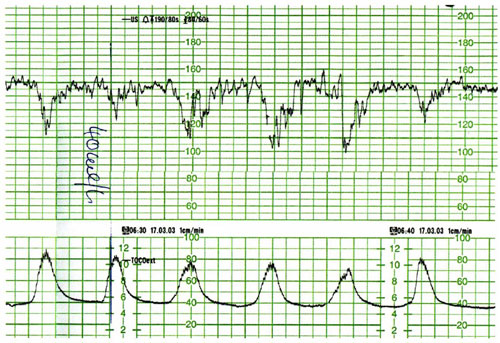

• CTG: Indikationen und Bewertung (DGGG, FIGO)

• Fallanalysen

• ...können CTG Aufzeichnungen nach aktuellen Kriterien beurteilen und vollständig

dokumentieren

• ...bewerten CTG Aufzeichnungen im klinischen Kontext angemessen